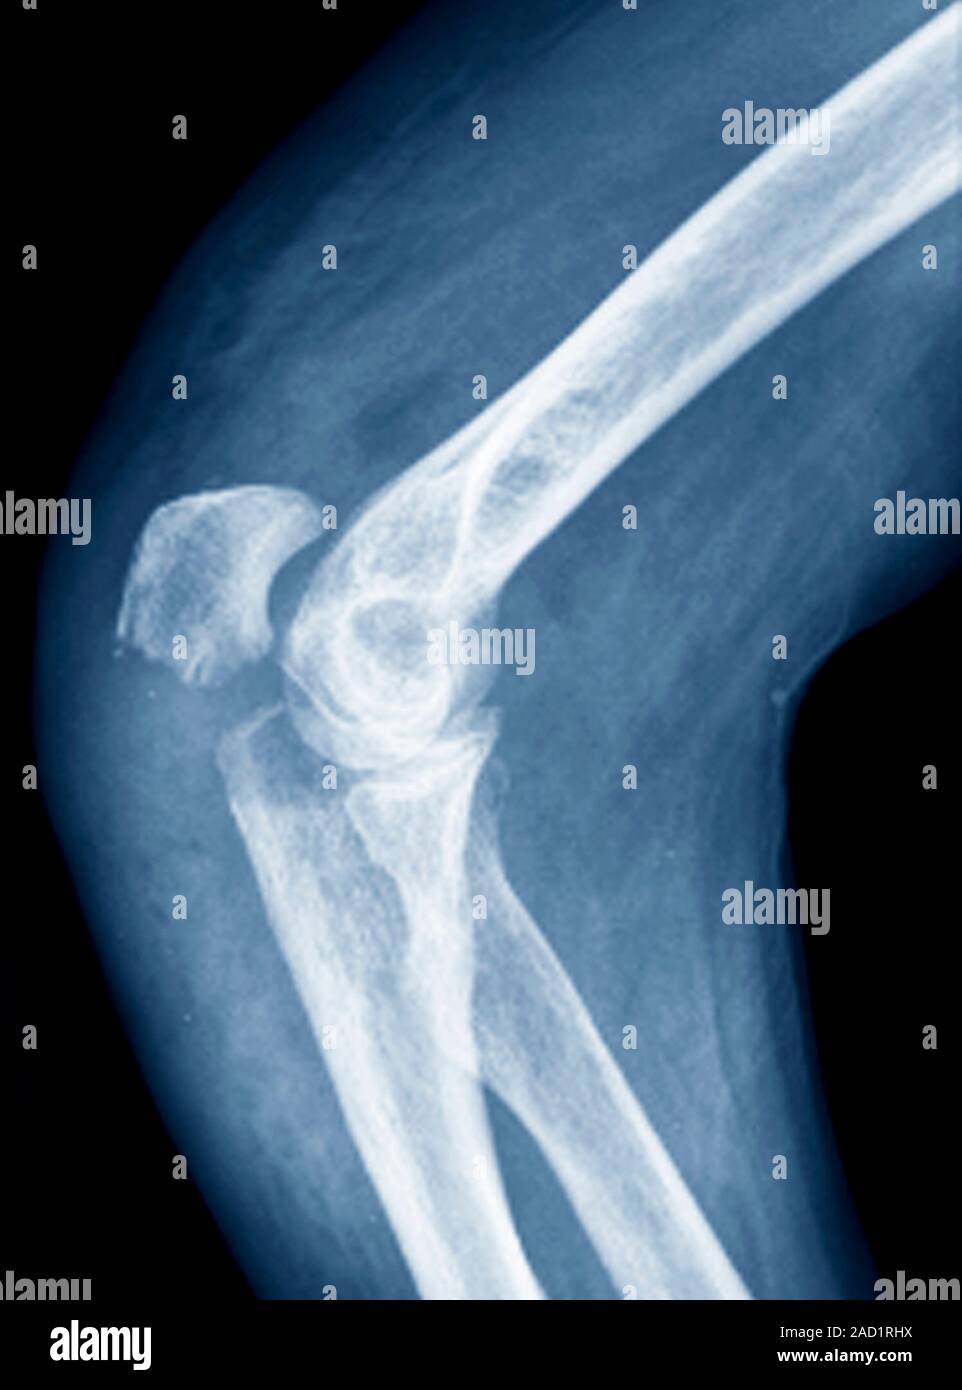

From www.sciencephoto.com

Fractured elbow, Xray Stock Image C017/7182 Science Photo Library Left Elbow Fracture X Ray What is the most common. Learn how to diagnose elbow fractures and dislocations with radiographs and ct scans. Learn about the elbow series, a set of radiographs taken to investigate elbow joint pathology, often in the context of trauma. Surgeons often get ct scans of elbows if they’re trying to. Check the anterior humeral line: Drawn down the anterior surface. Left Elbow Fracture X Ray.